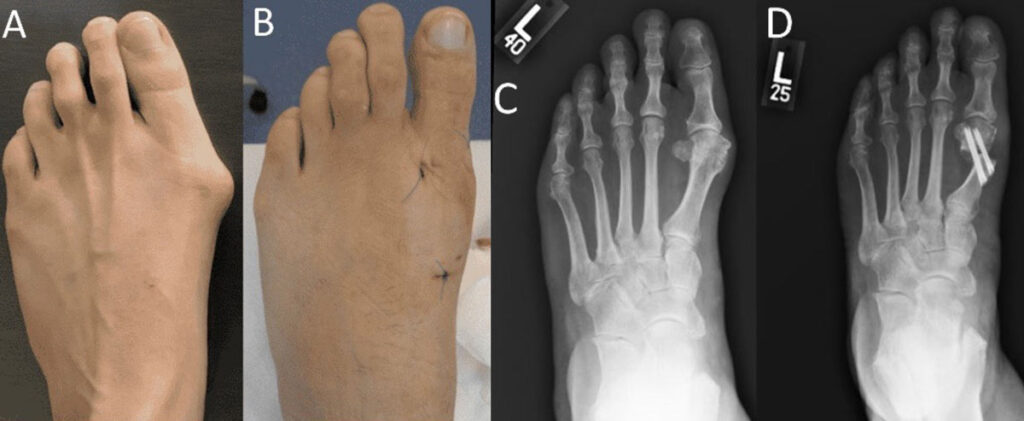

Hallux valgus (HV) is a common forefoot problem with a reported prevalence of 23% in adults age 18–65 years and 35.7% in adults aged over 65 years. More than a hundred procedures were described to treat HV deformity. Traditionally, surgical treatment of HV included open osteotomies and soft tissue procedures. In recent years, minimally invasive surgery (MIS) techniques have gained popularity because they can potentially provide decreased postoperative recovery period, smaller incisions, and a greater range of motion. [Figure 1 ]

Figure 1. A) Preoperative appearance of a patient with hallux valgus deformity. B) Minimally invasive hallux valgus surgery is performed with percutaneous incisions. C) Preoperative and D) postoperative anteroposterior radiograph of a patient underwent minimally invasive hallux valgus surgery.